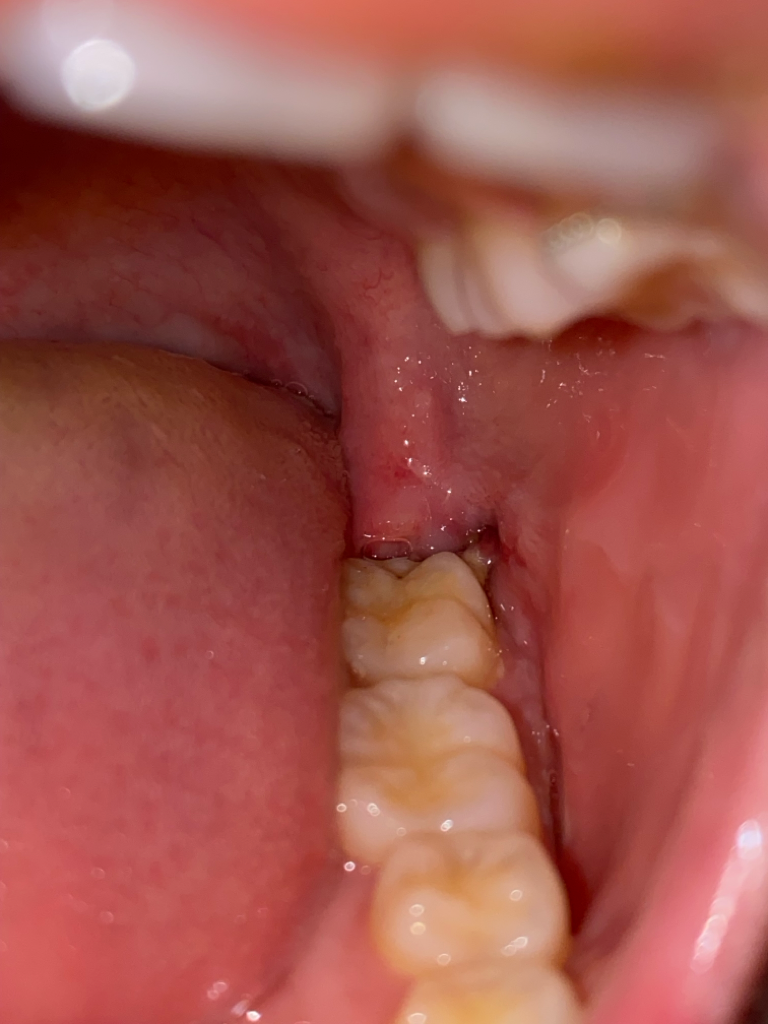

매복 사랑니 발치 5일 째 제대로 낫고 있나요?

현재 5일째입니다. 발치 후 2일째부터 실밥 부위에 극심한 통증이 있어서 4일차에 실밥 제거를 했습니다.

근데도 통증은 나아지지 않고 있으며 마치 구내염이 난 듯한 통증입니다. 일반식은 꿈도 못꾸고 있고 죽도 못 먹어 스프로 끼니를 떼우는데 반대 쪽 사랑니는 안 그랬었거든요. 의사쌤말로는 잘 낫고 있는 중이라고 하는데 너무 아파요. 잘 낫고 있는건가요? 그리고 잇몸 안의 노란색은 육아조직인가요?

• 1번 째 사진

육아조직은 염증조직으로 사진에 보이는 노란색은 육아조직이 아니라 음식물이 껴서 안빠진게 아닐까 생각됩니다.